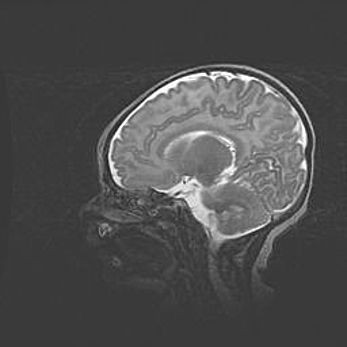

Наружная гидроцефалия с возможной атрофией височных областей.

Возраст: 28 дней

Вес: 3670 г

Пол: мужской

Окружность головы: 38 см

Срок гестации: 40 недель

Гидроцефалия головного мозга у новорожденных – это заболевание, которое характеризуется скоплением избыточного количества спинномозговой жидкости в желудочковой системе головного мозга в результате затруднения её перемещения от места выработки к месту поглощения в кровеносную систему или вследствие нарушения абсорбции. При открытой наружной форме гидроцефалии у новорожденных расширяются и переполняются субарахноидные пространства.

При нормотензивных  формах,  которые,  как  правило,  являются  следствием  перенесенных ишемических  повреждений  паренхимы  мозга,  возможно  сочетание микроцефалии  с нормотензивной гидроцефалией. В основе данных изменений лежит атрофия больших полушарий с преимущественной  локализацией  в  лобно-височных  областях.